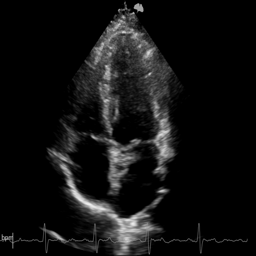

We evaluate on cardiac ultrasound videos from difficult-to-image patients using two unsupervised metrics: gCNR (contrast between ventricle and septum regions) and the KS statistic (agreement between original and denoised tissue distributions). Higher gCNR indicates better haze suppression; lower KS indicates better signal preservation.

Qualitative comparison on cardiac ultrasound dehazing. While both methods suppress haze (shown in the insets), RPCA tends to excessively attenuate tissue, resulting in sparse structures, whereas Nuclear Diffusion better preserves anatomical detail.